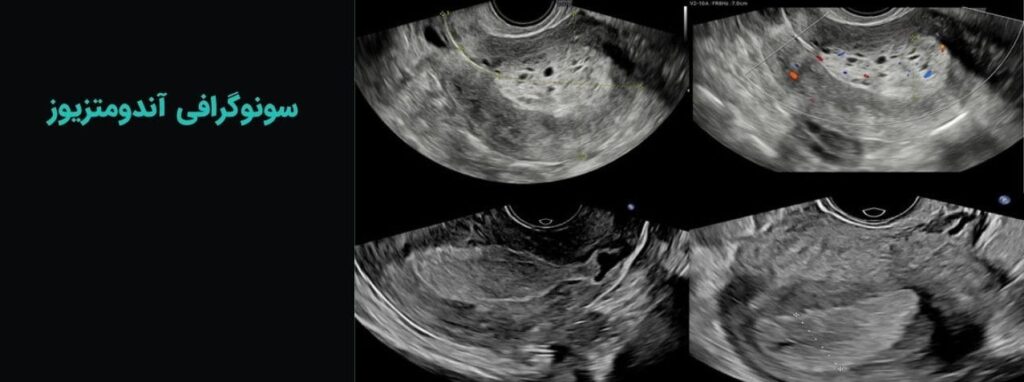

سونوگرافی

انواع سونوگرافیهای تخصصی سه بعدی، آنومالی و …